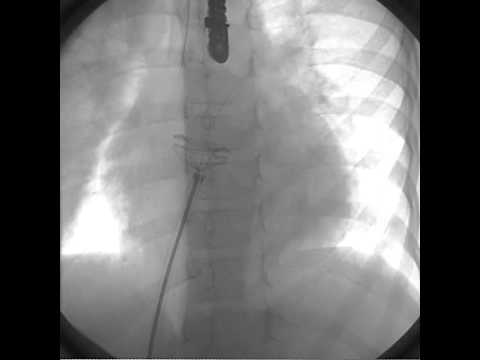

Transcatheter Closure - Movie 6: Pull and push on fluoro

Transcatheter Closure - Movie 8: Detachment on fluoro